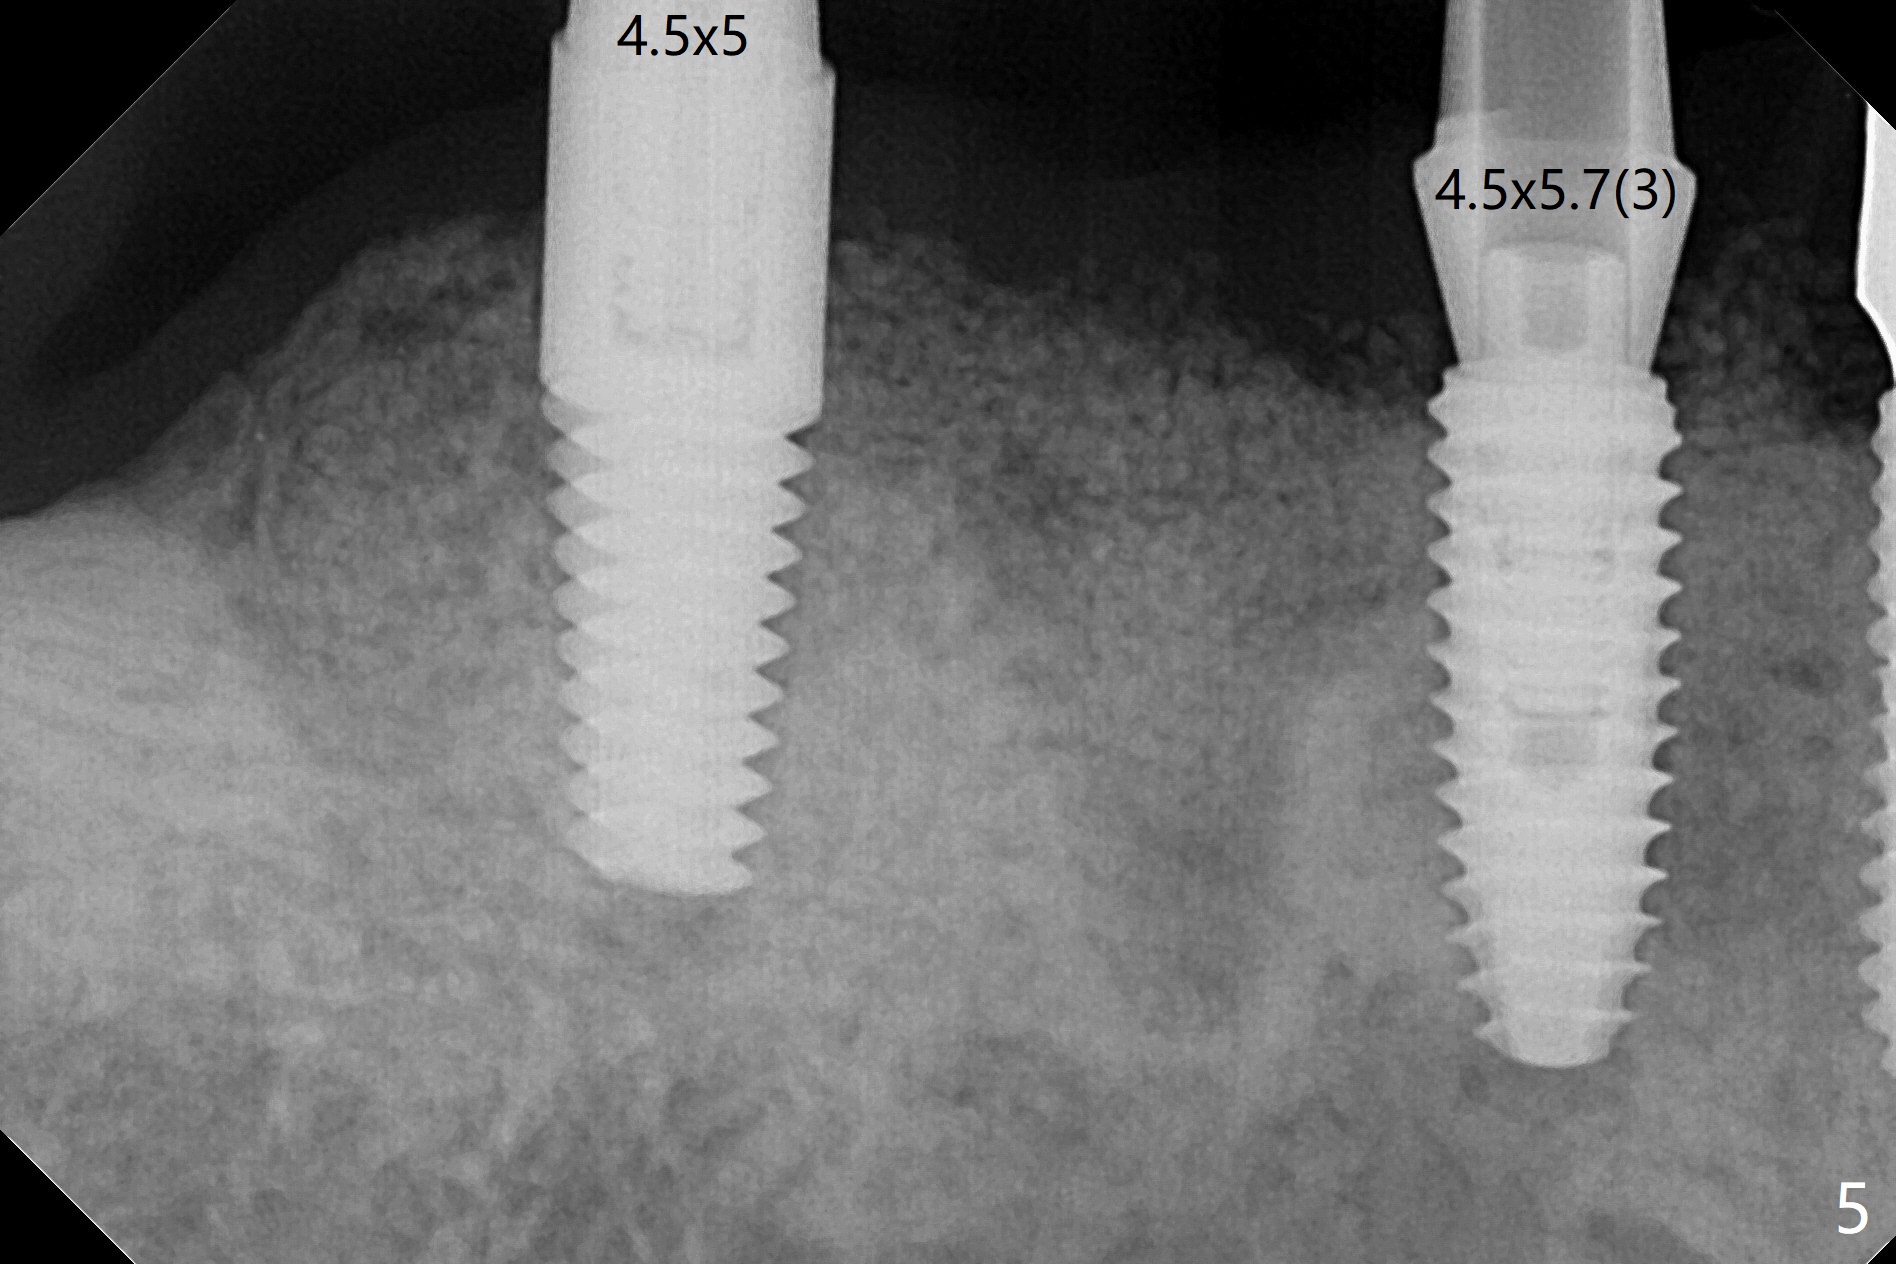

The ridge post bone graft (#28) and socket preservation (#30) is wide. Using a surgical guide (Fig.2), tissue punch is used to initiate osteotomy without compromising the keratinized gingiva (Fig.3). With no stop fixture mount for a 4.5x11.5 mm implant being placed at #28, the osteotomy at #30 is much easier. A 5x17 mm Tatum tapered tap is inserted with the guide and then without the guide. Finally the 5x14 mm tissue level implant is placed free hand (Fig.4). With underdrilling at #30 (4x10 and 4x11.5 instead of 4.5x10 and 4.5x11.5), primary stability is high. So is #28. Abutments are placed for periodontal dressing (Fig.5).